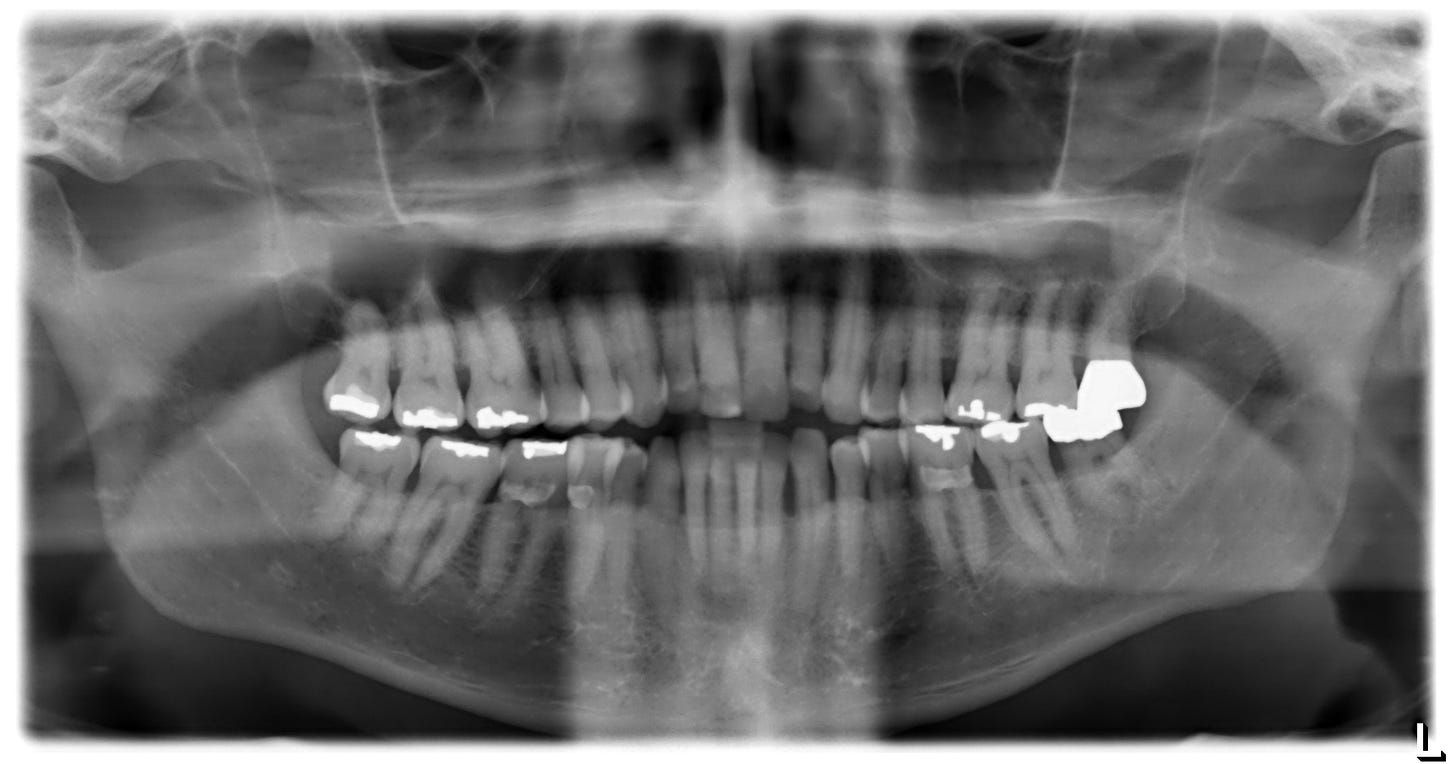

This is my “panorex” X-ray. My dentist counted seventeen amalgams last week. This is a lot of metal, and these were originally 50 percent mercury. Typically, about half of it dissolves from the teeth and passes into the rest of the body over about twenty-five years. Mine are older than that.

I wonder if my recent tremor and lifelong low-grade anxiety are due to mercury toxicity from my childhood amalgams. Also, replacing my shoulders recently may have mobilized mercury due to battery effects. So I am getting all seventeen fillings removed and replaced with white “composite.” (Saremco ceramic composite fillings might be the best.) This material is more expensive, harder to use, and less profitable for dentists. Once the mercury source is gone, the rest gradually clears from the body, but chronic cases may not improve symptomatically. Wish me luck.